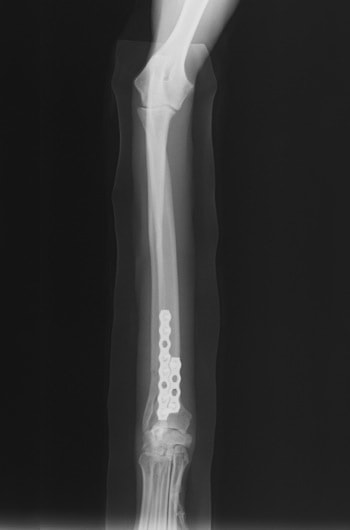

トイプードル 右遠位橈尺骨短斜骨折のALPSによる内固定